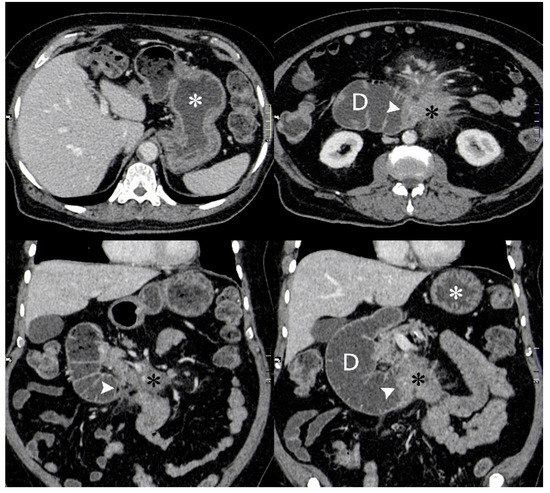

Computed Tomography (CT) of his chest, abdomen and pelvis showed a large (8 cm × 10 cm × 9.5 cm) mesenteric mass encasing the mesenteric vessels with proximal small bowel obstruction (Figure 2). There were multiple enlarged mesenteric and retroperitoneal lymph nodes.

Axial (top row) and coronal (bottom row) CT images from an initial diagnostic portal venous phase contrast enhanced CT when patient presented with symptoms of gastric outlet obstruction. Fluid filled dilated stomach (white asterisk) and 2nd and 3rd part of duodenum. Ill-defined enhancing mass in the root of the mesentery (black asterisk) obstructing the 3rd part of the duodenum (white arrowhead).

A repeat CT scan of his abdomen (Figure 7) confirmed secondary loss of response. Radiotherapy to the mesenteric mass was considered, however, he unfortunately developed gastrointestinal bleeding, which precluded this.

Follow up axial (top row) and coronal (bottom row) venous phase contrast enhanced CT images performed 11 months after initial diagnostic CT when patient represented with symptoms of reduced appetite and abdominal swelling. The degree of gastric dilatation (white asterisk) is considerably less than on the initial CT. The mesenteric mass (black asterisk) has significantly reduced in volume following chemotherapy but the duodenum (D) is more dilated and obstructed at the 3rd part (white arrowhead), possibly due to post treatment fibrosis.